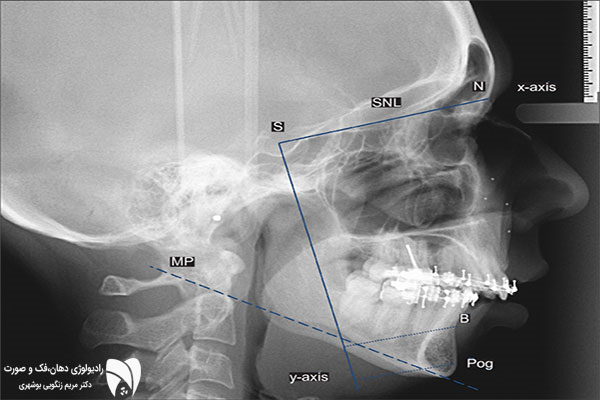

در عکاسی پرتره، هدف اصلی ثبت تمام صورت از بالای سر تا گردن در ۳ حالت اصلی است: لب ها کنار هم، دهان باز و لبخند کامل. از این نوع تصاویر برای تحلیل زیبایی و تقارن صورت استفاده می شود.